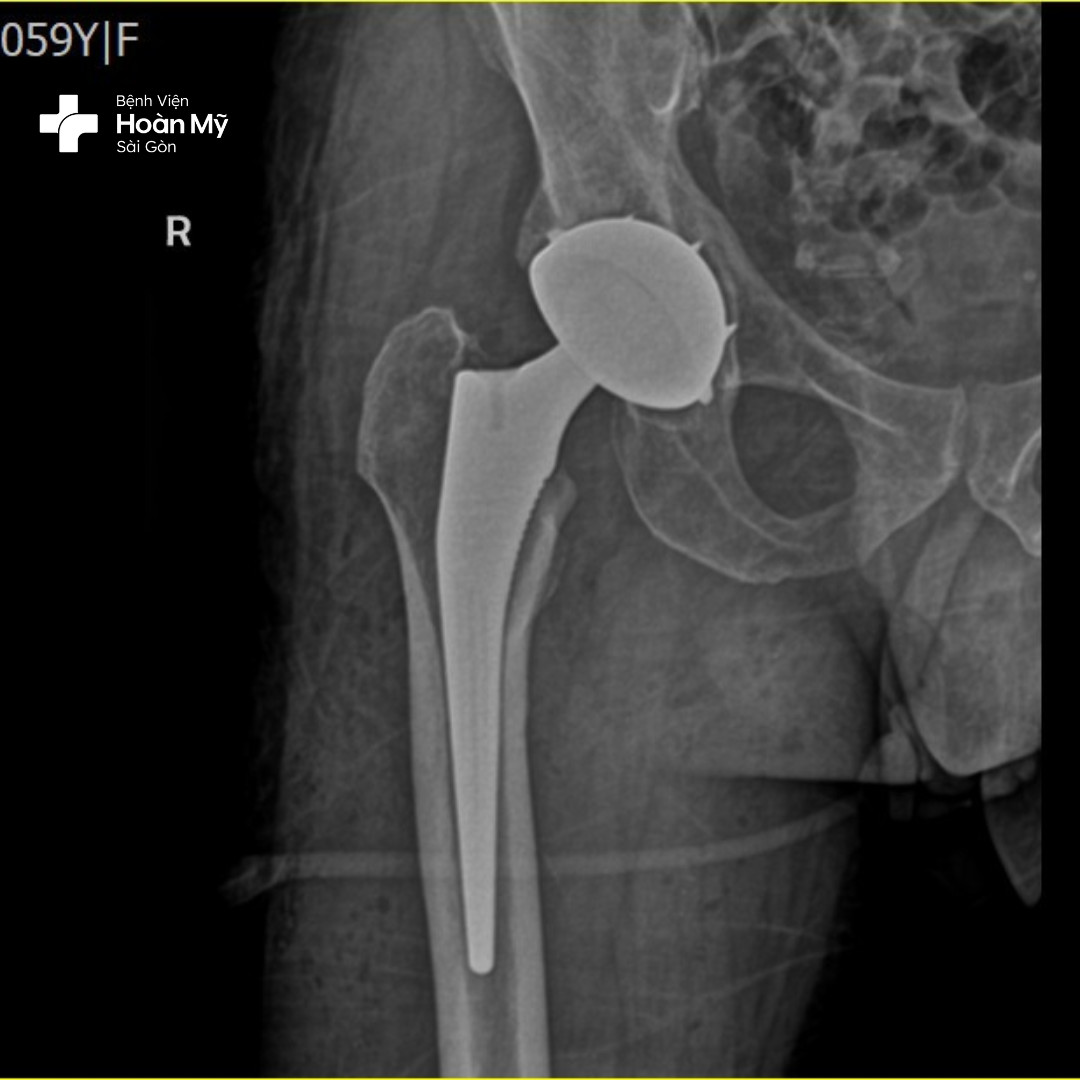

Hình ảnh X-quang sau phẫu thuật thay khớp háng của người bệnh

Thay khớp háng toàn phần

Thay toàn bộ phần mặt khớp của xương đùi và ổ cối. Phẫu thuật này được chỉ định khi bệnh nhân bị các tổn thương khớp như thoái hóa, hoại tử vô khuẩn… và kỹ thuật này có thể thực hiện thay 2 bên cùng lúc giúp bệnh nhân lấy lại chức năng vận động sớm hơn.

Thay khớp háng bán phần:

Chỉ thay thế phần chỏm xương đùi mà không thay thế ổ cối; đây là phẫu thuật được chỉ định các trường hợp chấn thương gãy cổ xương đùi ở người già, hoặc những trường hợp thể trạng yếu không thể đảm bảo thực hiện thay khớp háng toàn phần.

Kỹ thuật tiên tiến này được thể hiện trong quá trình phẫu thuật thay khớp háng, bác sĩ phẫu thuật chỉnh hình tại bệnh viện Hoàn Mỹ Sài Gòn sẽ THAY THẾ cả HAI đầu khớp háng bị hư hỏng bằng các bộ phận nhân tạo cùng một lúc giúp người bệnh không phải chịu đau 2 lần, tránh được biến chứng phẫu thuật, tiết kiệm về tài chính. Đây là kỹ thuật đòi hỏi tay nghề cao của bác sĩ có nhiều năm kinh nghiệm.